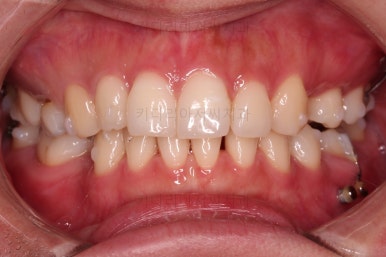

임플란트 보철까지 잘 세팅이 된 후 마무리 하게 되었습니다.

임플란트까지 잘 들어간 후 마무리 했고요.

결손공간 없이 상하좌우 모두 같은 갯수의 치아로 치료가 잘 종료되었습니다.

부산인비절라인 전후 비교해 볼게요.

가장 신경쓰였던 부분이 입매가 양호한 상태에서, 추가 발치에 결손공간까지 폐쇄 해야 하는 상황이어서 입이 더 들어가지나 않을까 하는 점이었는데요.

매우 세심한 컨트롤로 입매는 매우 양호하게 잘 마무리가 되었습니다.

당연히 빈공간에 대한 처리도 잘 되었고요.

얼굴에 대한 중앙선도 잘 마무리 되었습니다.

만약 이 상황에서 좀 더 예쁘게 하고 싶다면 왜소치아를 크기를 키운다면 중앙선의 앞니의 느낌이든 좀더 나아질 수 있었을텐데, 이 부분은 필수가 아니니깐요.

어쨌든 모든 부분에서 인비절라인으로 잘 마무리가 된 환자분이었습니다.

이상 결손치아가 5개 있었고, 비대칭, 유치잔존 환자분을 부산인비절라인으로 교정치료 후 임플란트 2개로 마무리를 한 치료사례였습니다.